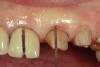

The most common reasons to extend a margin below tissue are: caries below gingiva; old restorations that already exist below gingiva; to achieve adequate tooth preparation length for proper retention and resistance; to make significant contour alterations; to hide the margin when the tooth is discolored (Figure 3 and Figure 4); and to hide the margin when the restorative material of choice demonstrates optical properties different from those of the natural tooth such that the margin would be highly visible. Regardless of why a subgingival margin is chosen, there are 2 negative responses that may occur.

Figure 3  Dark teeth or teeth requiring restorations that are more opaque for masking often require the margin to be carried subgingivally, as with this central and lateral incisor.

Figure 3

Figure 4  View of the completed central and lateral incisor with margins placed subgingivally, but maintaining tissue health.

Figure 4